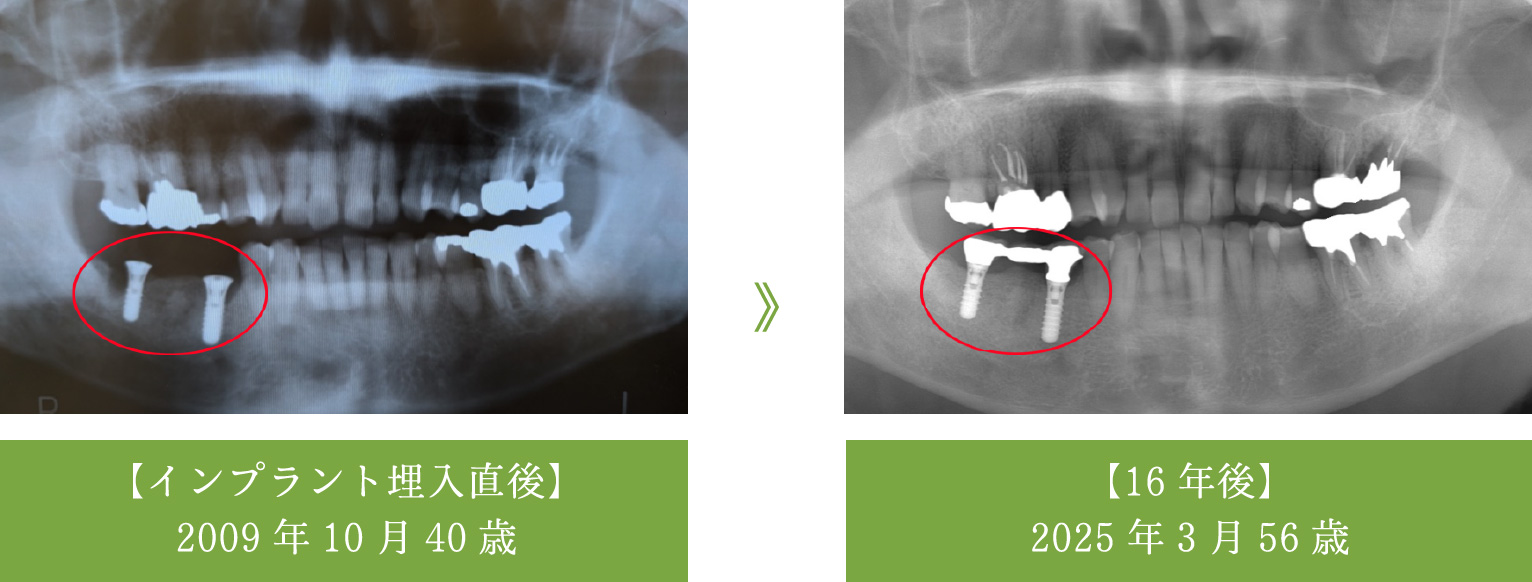

インプラントの16年経過症例-1

【60代で治療→80代現在も良好】他の歯を守るインプラント

- 歯根破折により右下の奥歯を喪失

- インプラント2本を埋入し、しっかりと噛めるブリッジを作製

- 治療から16年経過し、83歳となられた現在もトラブルなく機能しています。

インプラントがしっかりと噛む力を支えているため、この16年間、他のご自身の歯を一本も失うことなく過ごされています。 - メンテナンス

- 3~4ヶ月ごとに歯科衛生士によるパウダークリーニングを実施

- 期間:5ヶ月(12回)

- 費用:88万円(当時の価格/インプラント手術 44万円)

(インプラント2本埋入、被せ物 44万円)

- リスク:術後の腫れ(ピークは3日目程度)、全身疾患の有無確認が必要